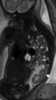

Crossed renal ectopia

Crossed dystopia (syn.unilateral fusion cross fused renal ectopia) is a rare form of renal ectopia where both kidneys are on the same side of the spine. In many cases, the two kidneys are fused together, yet retain their own vessels and ureters. [Source: Wikipedia ]